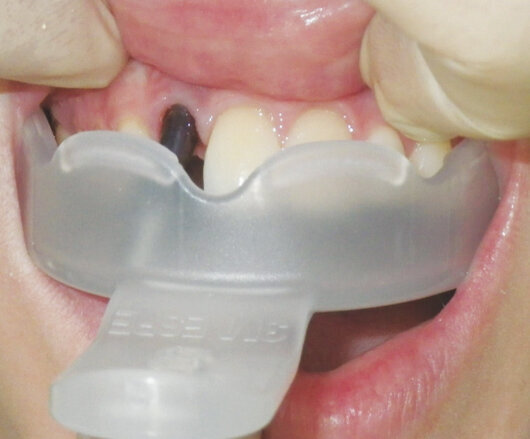

A marking medium was placed on the top surface of the implant impression screw and this marking was transferred to the inside of the tray by seating the tray intraorally (Fig. 3). An acrylic bur was used to create a hole in the base of the tray (Fig. 4) and the impression tray was then tried in the mouth to ensure that there was clear access to the impression screw (Fig. 5).

Fig. 5: The 3M™ Directed Flow Impression Tray is being tried in the mouth to make sure that the impression screw is accessible.